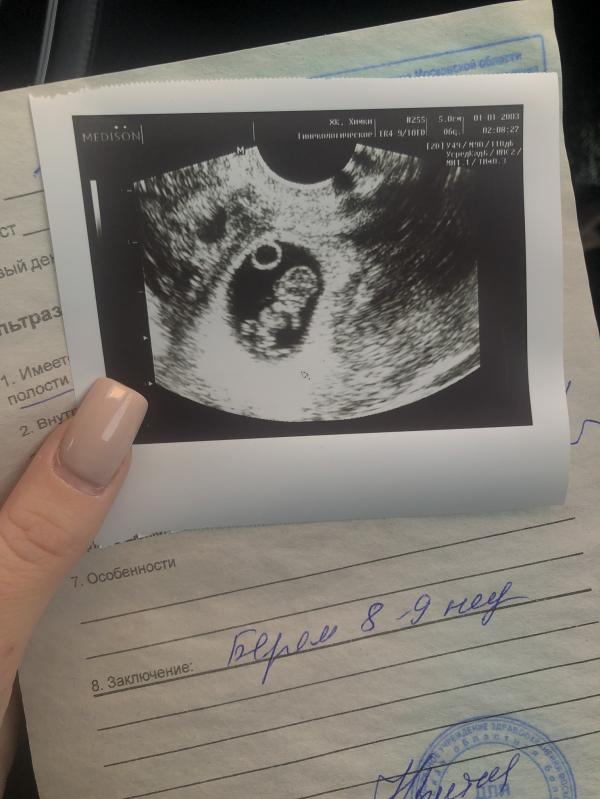

Что - то я все с вопросами, да с вопросами, я сегодня вот на узи первом была, господи, услышала звук сердечка чуть с ума не сошла, врач аж спросила (это вы от перемены настроения такая или всегда 😹), а я впринципе очень эмоциональный человек 😅 сказала, что все хорошо, показала, там такой уже целый человек, так интересно это всё, женский организм - мощь, когда знаешь теорию - это совсем другое 😱 практика намного лучше 😅